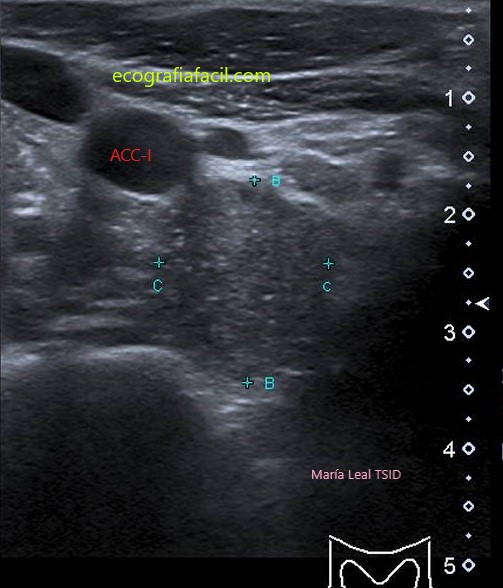

LISO:

MAL DEFINIDO: